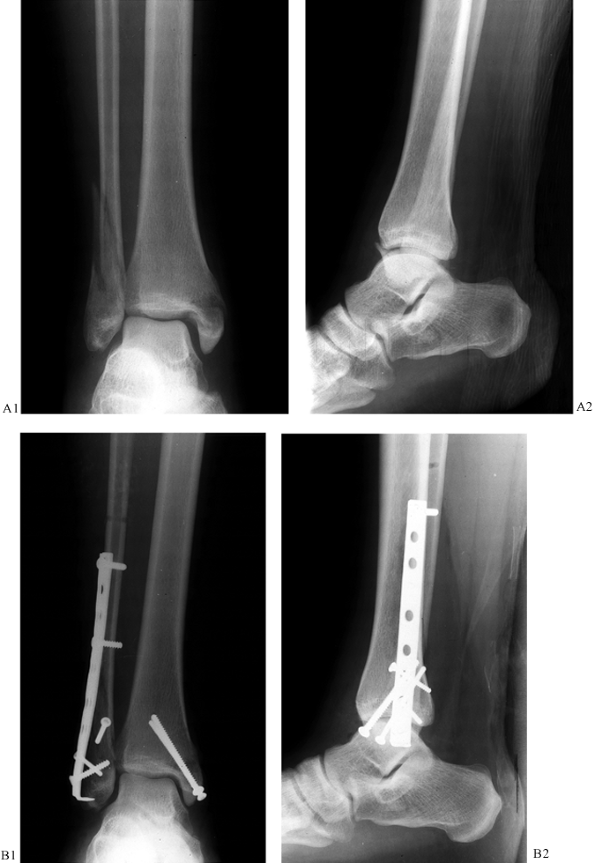

unstable for emergent surgery into calcaneal pin traction on a Boehler

frame and allow the traction to regain length and alignment of the

limb. Elevation, reduction, and time allow the posttraumatic

inflammatory period to pass. An idea of the relative ease of open

reduction and internal fixation may be obtained by viewing radiographs

of the reduction obtained by pure distraction during the traction

period (23,24) (Fig. 25.22).

![]() |

|

Figure 25.22. A:

Anteroposterior (AP) radiograph of a type C pylon fracture. Notice the shortening that contributes to displacement of the diaphyseal and articular fracture fragments. B: An AP radiograph of the same fracture with 10 kg (22 lb) of skeletal traction applied through the calcaneus. Notice how simple distraction has reduced most of the diaphyseal and epiphyseal fracture displacements. This is a good prognostic sign, indicating that indirect methods of reduction during surgery can allow an atraumatic reduction of the fracture, which then may be fixed by standard methods of internal fixation. C: Another AP projection of a type C pylon fracture. Although this fracture is more comminuted than the previous example, a more important indicator of problems in reduction during surgery is shown by its failure to reduce or improve with skeletal traction. D: Ten kilograms (22 lb) of traction applied to the calcaneal pin have not markedly improved the radiographic situation. Failure to improve during skeletal traction can be attributed to the interposition of soft tissue. In this fracture, the flexor hallucis and neuromuscular bundle have been displaced into the joint and block reduction of the posterior fragment. |